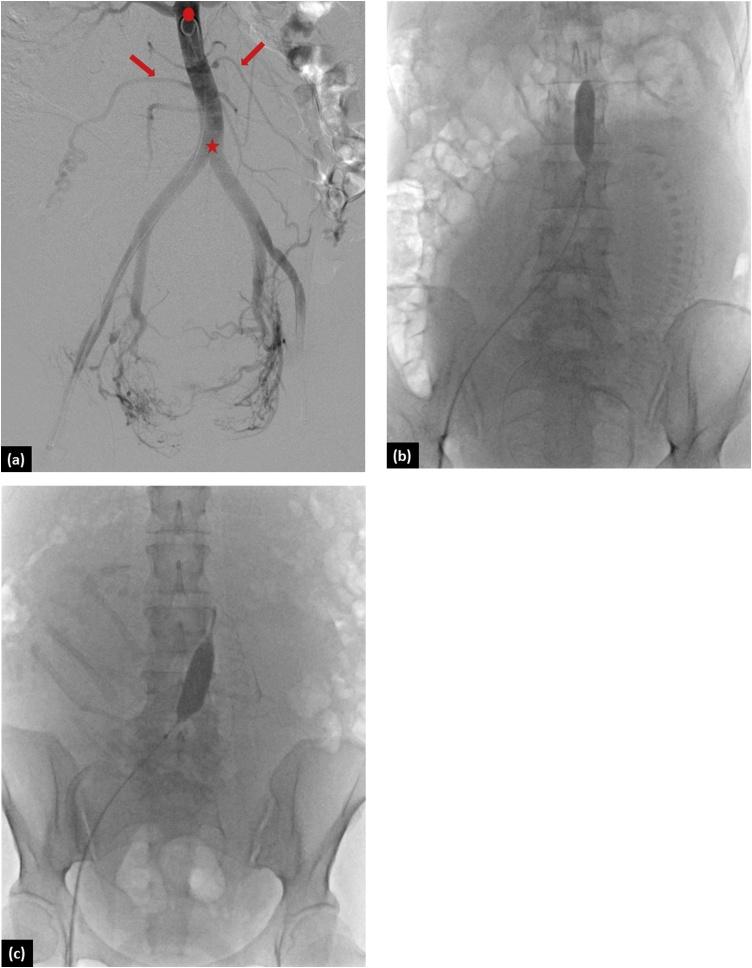

Thirty-two pregnant women with coexisting placenta accreta and placenta previa treated with PABO in our hospital during 2013-2020 were retrospectively analyzed. The patients were divided into two groups: one with infra-renal abdominal aortic balloon occlusion above the ovarian artery (Group A, n = 15) and the other with occlusion below the ovarian artery (Group B, n = 17). Medical records and relevant imaging of all patients were reviewed. All Cesarean deliveries were scheduled and we decided to perform hysterectomy based on the surgical findings.

Patients in both groups were similar in terms of age, gravidity history, and status of placenta. Regarding their outcomes, estimated blood loss was not significantly different in both groups, although it was lower in Group B than in Group A (3949.5 vs. 4333.8 ml). The other tested parameters did not show any difference. The uterus was preserved in 13 (41%) patients. No access-related or balloon occlusion-related complications occurred in either group.

PABO was safe. However, the balloon location (above or below the ovarian arteries) did not influence the outcomes. Further evaluation and prospective studies are required to evaluate the safety and efficacy of balloon occlusion above or below the ovarian artery in patients with coexisting placenta accreta and placenta previa.